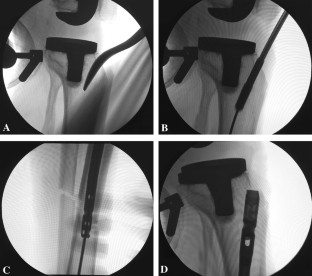

Between 2017 and 2018, three patients with acute tibial shaft fractures distal to a TKA (Felix Type 3A) were treated with an intramedullary nail. Preoperative planning involved assessing proximal tibia to ensure adequate room for implant and instrumentation. The average patient age was 66.3 years (range 59–72 years) and all patients were males. All the patients sustained fractures of distal tibial and fibula diaphysis, after a road traffic accident. There were no complications intraoperatively, and all procedures were completed uneventfully. One patient underwent additional fixation of the fibula.

We recommend that this technique can be used primarily for this fracture pattern distal to a TKA, provided there is adequate space to accommodate the nail and instrumentation proximally anterior to the tibial tray.

Fig. 2